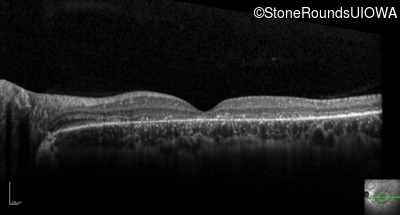

Optical Coherence Tomography - Right - 10/200

Exemplar / OCT Stack

OCT Stack